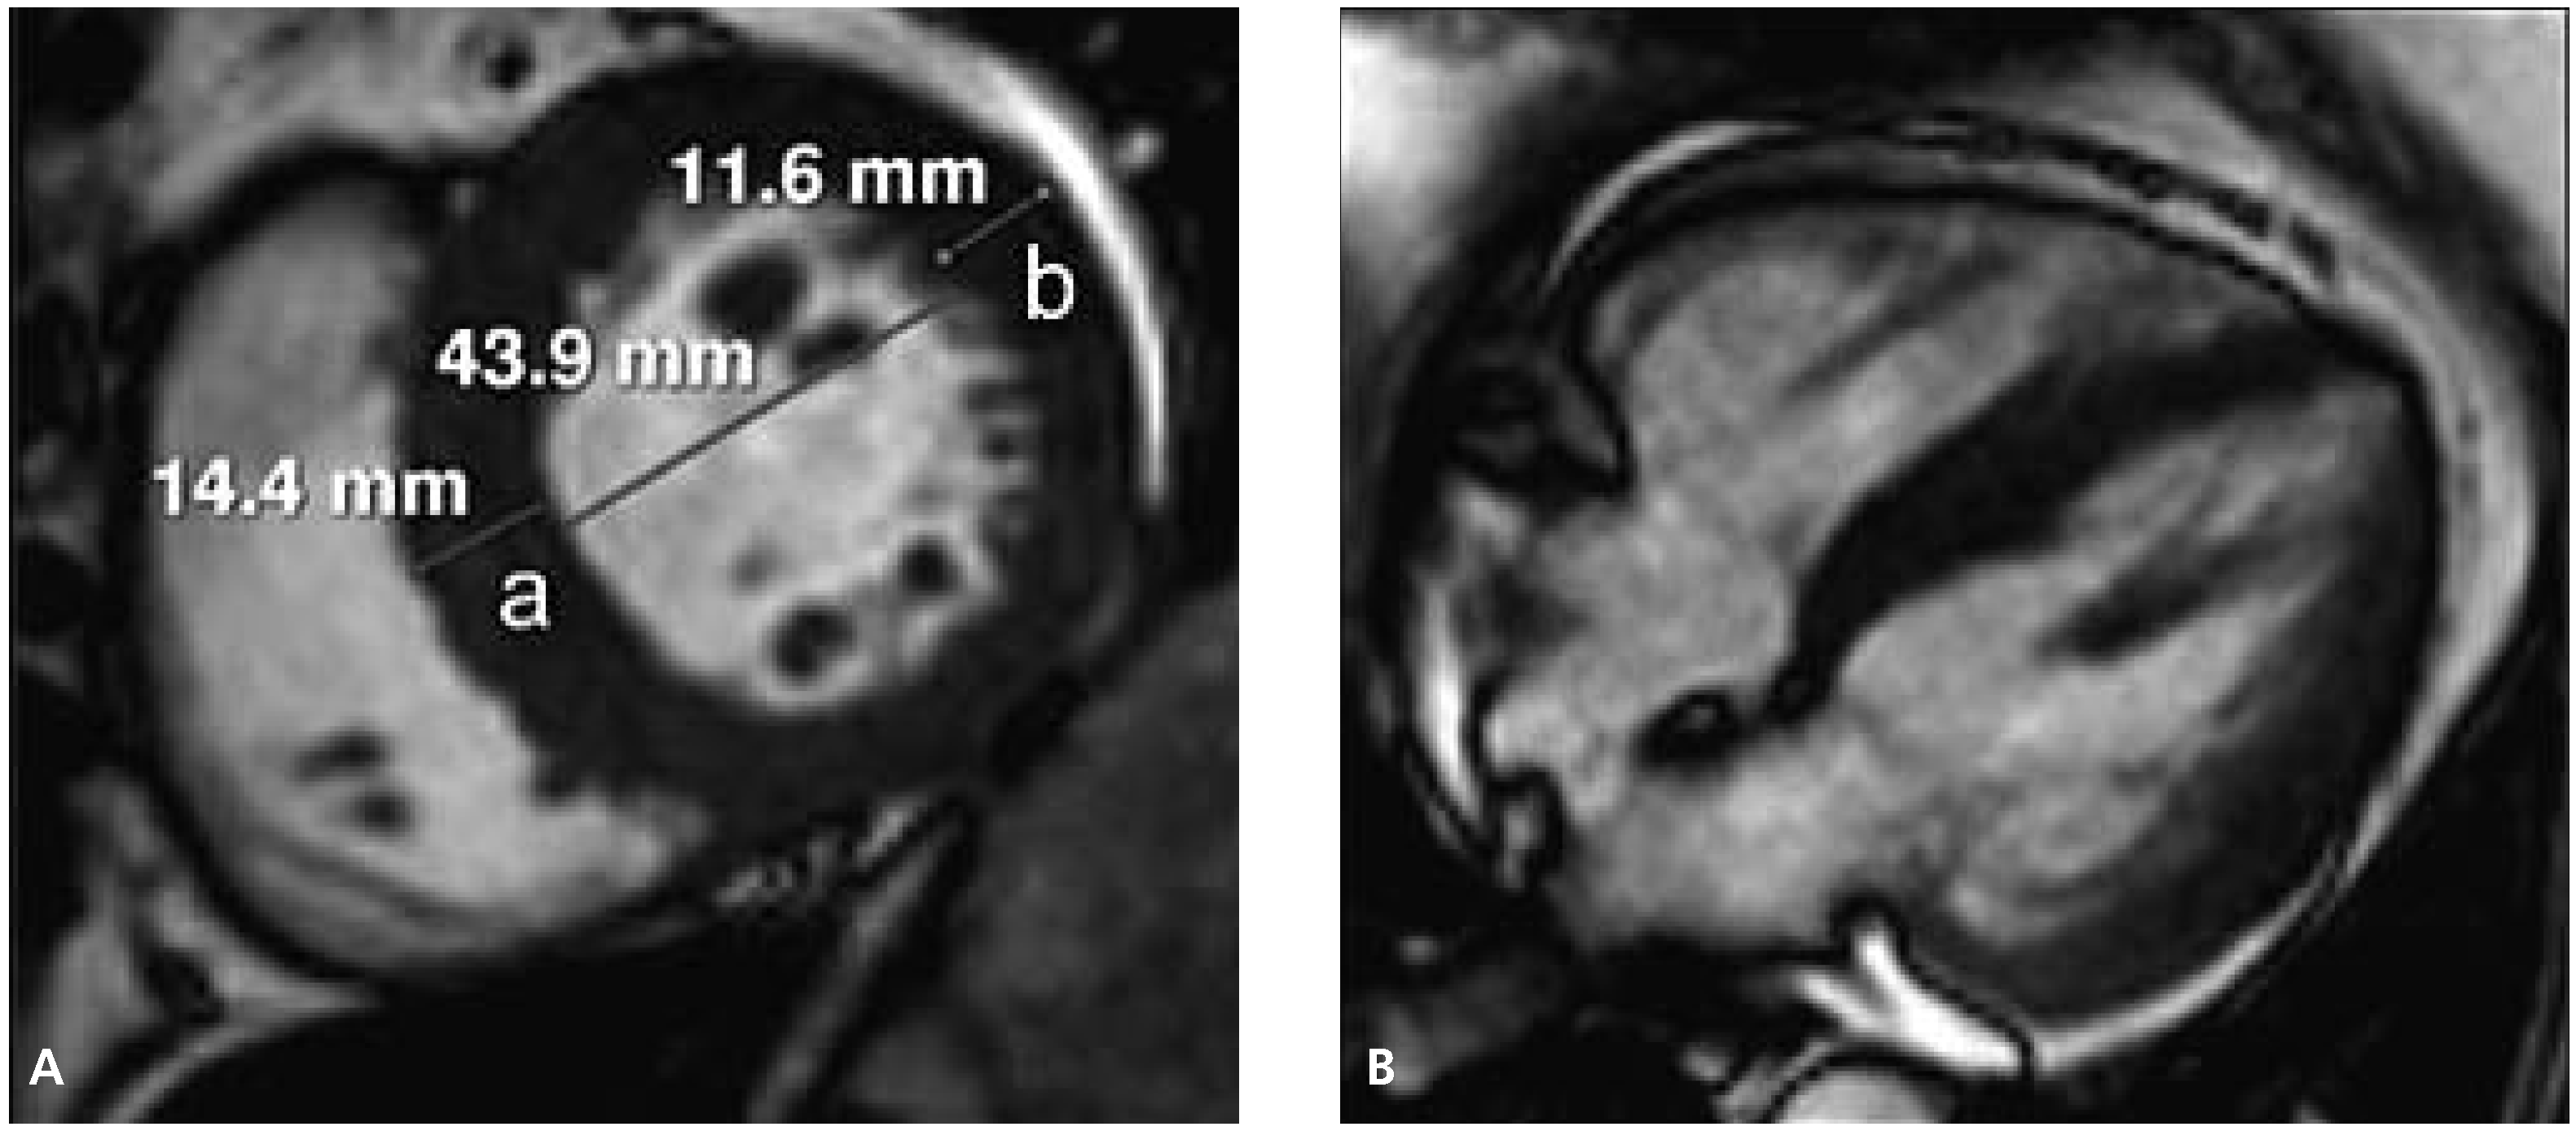

Abbildung 1.

Herz-MRT. A Darstellung des Herzen in der kurzen Achse: a = Wanddicke des Kammerseptums (normal <11 mm); b = Dicke der Lateralwand (normal <11 mm). B Vierkammerblick des Herzens.